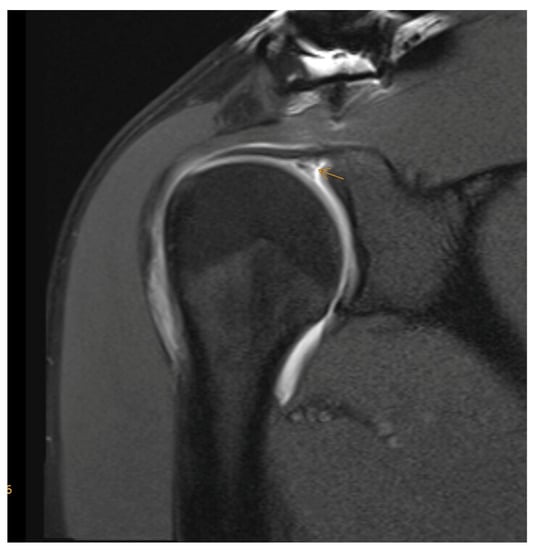

3.1. Magnetic Resonance Imaging (MRI) versus MR Arthrography (MRA)

- Magee, T. 3-T MRI of the shoulder: Is MR arthrography necessary? AJR Am. J. Roentgenol. 2009, 192, 86–92. [Google Scholar] [CrossRef]